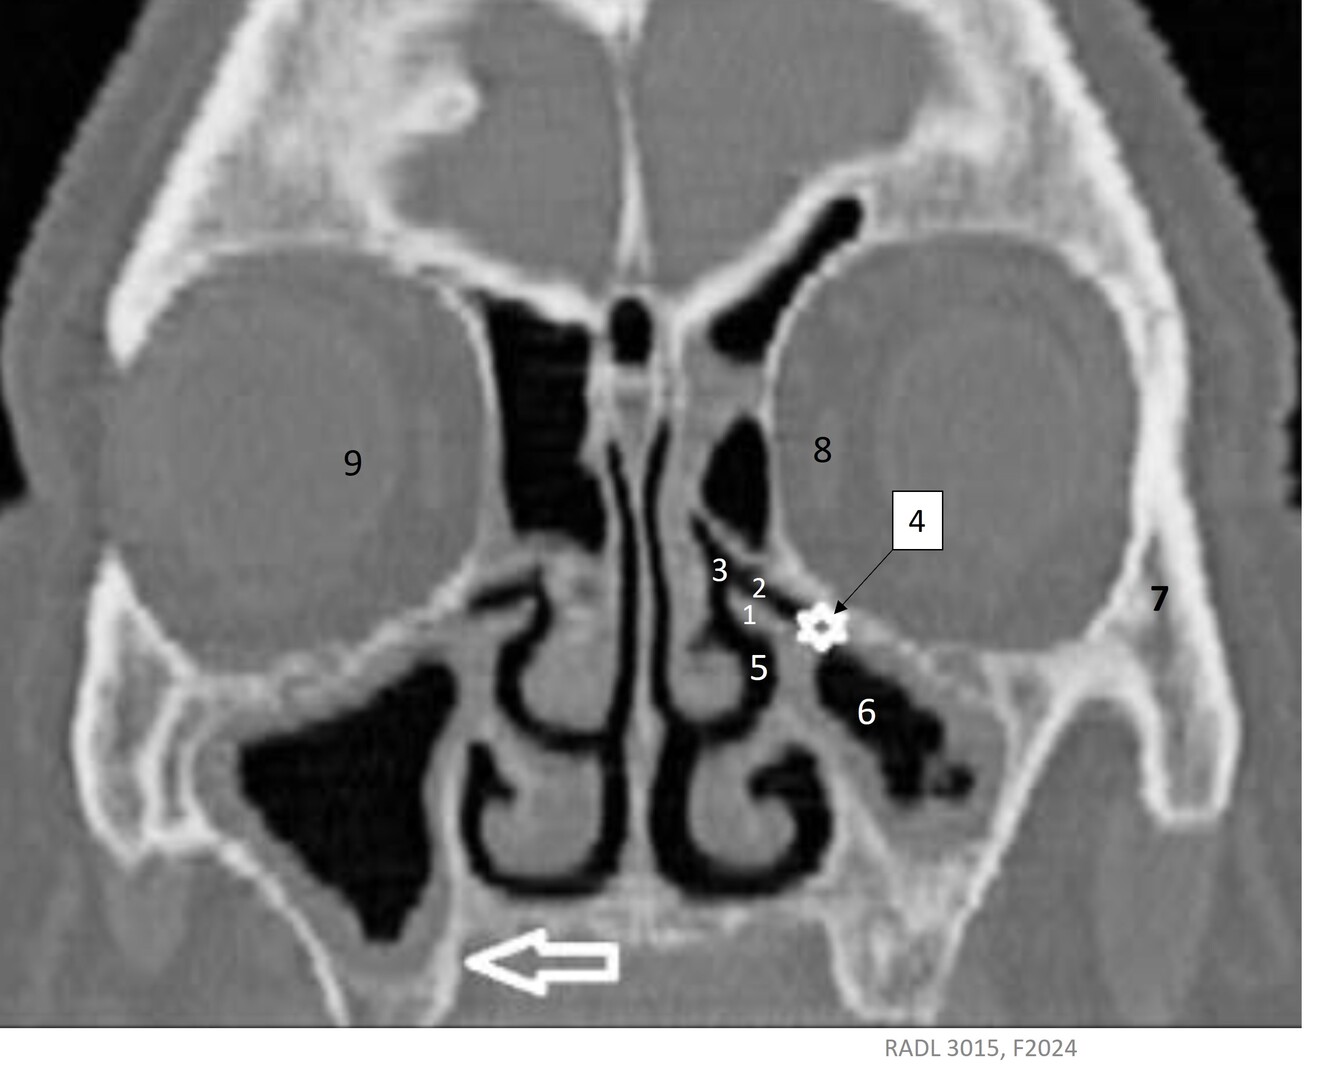

21

Label 1-9

A

1=Lt uncinate process

2=Lt infundibulum

3=Lt hiatus semilunaris

4=Lt ostium (mandible)

5=Lt middle nasal meatus

6=Lt maxillary sinus

7=Lt Zygoma

8=Lt medial rectus muscle

9=Rt globe of eye